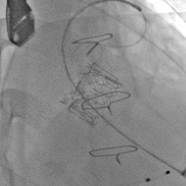

术前经详尽评估患者病情,通过CT重建测量瓣环直径、左室流出道面积。结合之前外科换瓣手术入路,最终决定采用经心尖途径行二尖瓣“瓣中瓣”手术,患者既往植入27#爱德华猪瓣,选用25# Renato®球扩式瓣中瓣。手术过程顺利,瓣中瓣植入位置理想,功能表现出色,左室造影及经食道超声观察无明显瓣中及瓣周反流。二尖瓣峰值流速由术前2.1m/s降至1.0m/s,平均跨瓣压差由7.2mmHg降至1.8mmHg。

瓣膜释放

瓣中瓣术后